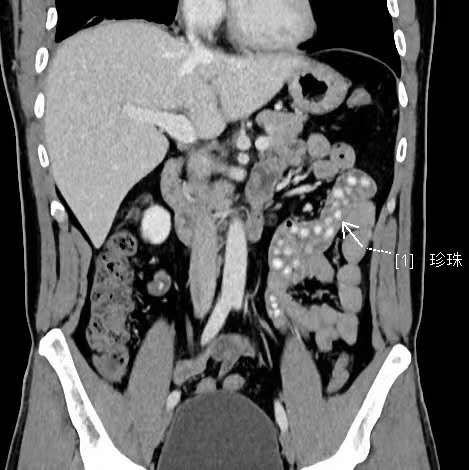

拍出來的片子讓醫(yī)生大吃一驚,小林的胃腸道里布滿了高密度陰影。仔細一看,醫(yī)生發(fā)現(xiàn)是一顆顆沒有消化的東西,像珍珠奶茶里面的“珍珠”。

“密密麻麻,粗略估計有幾十顆。”影像科副主任醫(yī)師薛貞龍告訴現(xiàn)代快報記者,奶茶里的珍珠很難消化,CT顯示腸腔內(nèi)圓形結節(jié)狀高度密影。他提醒,對于炎性腸病患者,尤其是伴有輕中度腸道狹窄的患者,最好別喝奶茶,很容易誘發(fā)腸梗阻。